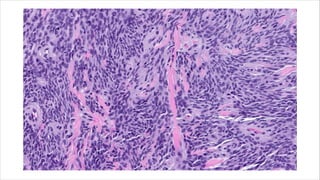

• Arranged into nests or cords and embedded into hyalinized

stroma.

• Spindled cells with varying amounts of hyalinized and myxoid

• Arcuate vessels and hyalinized collagen rosettes seen.

Immunochemistry:-

• Positive for low grade fibromyxoid stroma.

• EMA positive, cytokeratin, S100, SMA, desmin and CD34 stains are

negative.